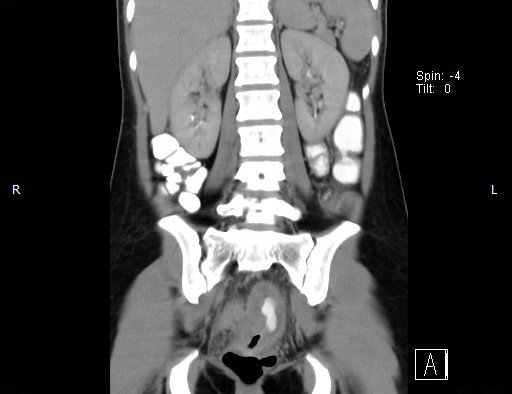

Abdominal CT images

CT finding : Circumferential rectal wall thickening-> Tissue diagnosis -> Rectal cancer

CT finding correlated with plain abdominal radiograph